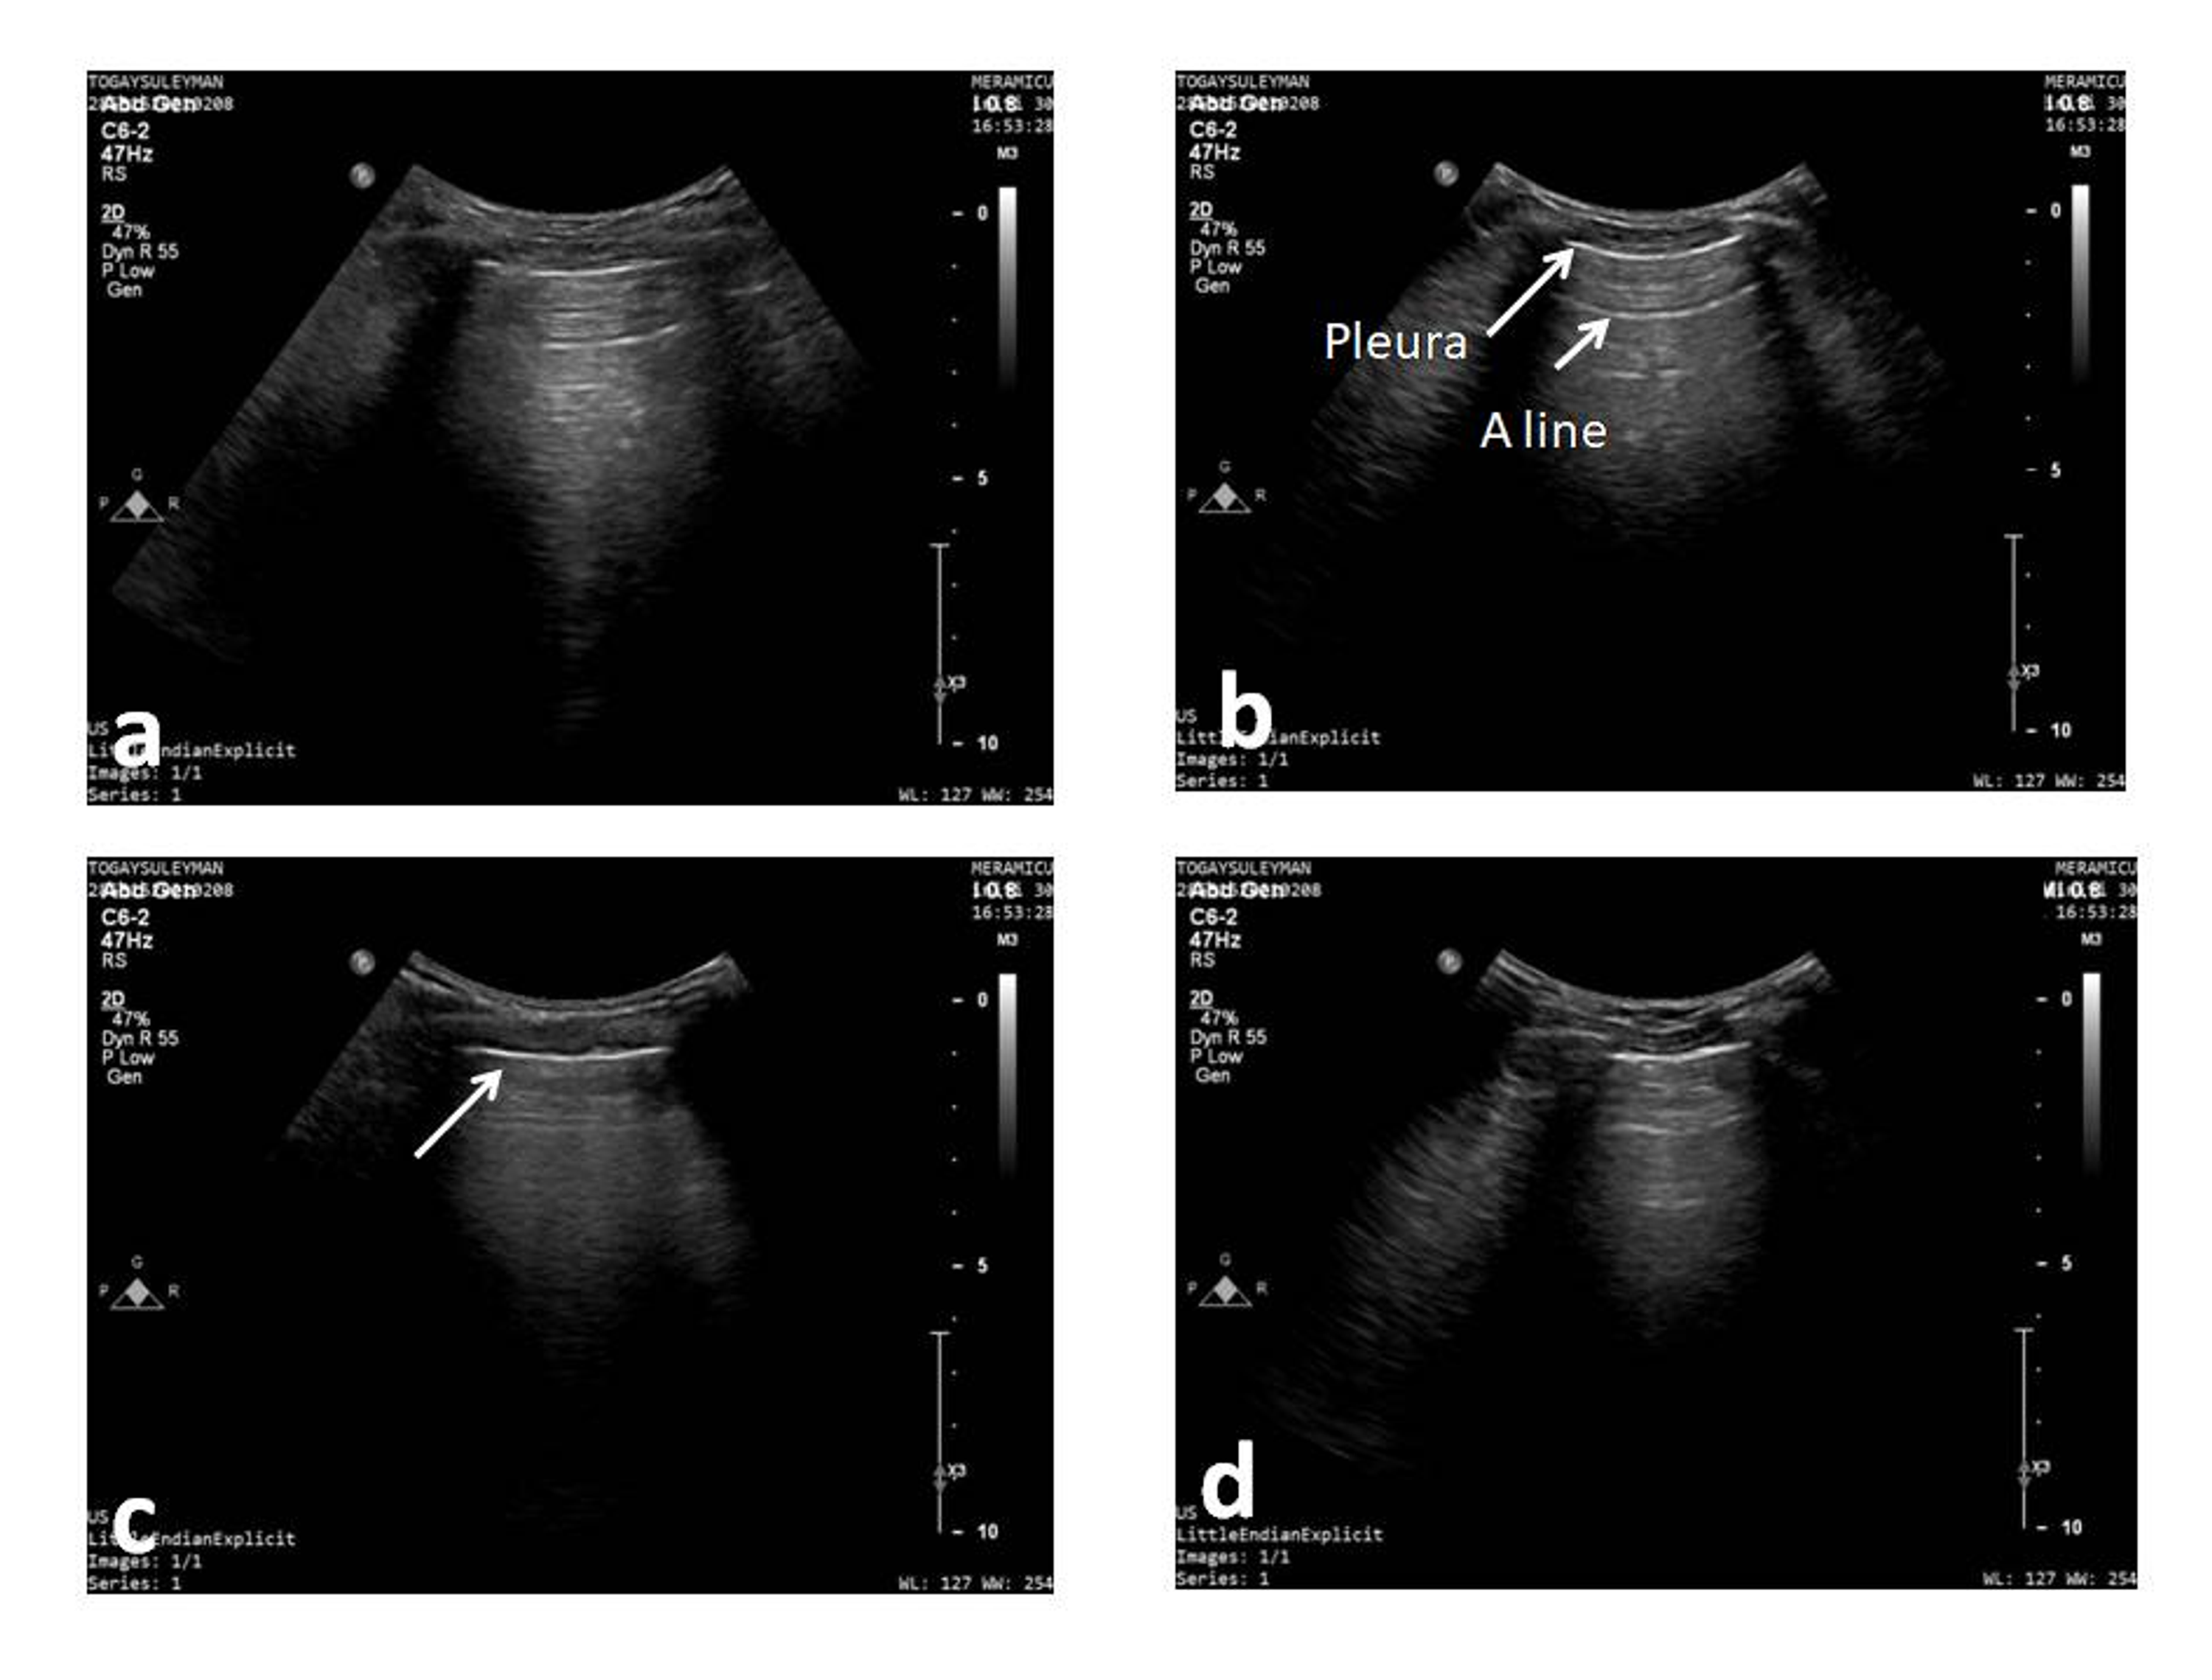

Frontiers Case Report Lung Ultrasound in Critically Ill Neonates Diaphragmatic Ultrasound In Critically Ill Patients Abnormal diaphragmatic mobility (reduced, absent, or paradoxical movement) can be indicative of dd. Considering the relevance of diaphragmatic dysfunction in critically ill patients, the current literature has been committed to prioritizing the care of patients under mv in order to monitor diaphragm function in the icu and to minimize or avoid diaphragm myotrauma to prevent the development of vidd [18].. Diaphragmatic Ultrasound In Critically Ill Patients.

JCM Free FullText Current Advances in Lung Ultrasound in COVID19 Diaphragmatic Ultrasound In Critically Ill Patients Furthermore, in critically ill patients, the reduced diaphragm perfusion elicited by mechanical ventilation facilitates effective redistribution of. Considering the relevance of diaphragmatic dysfunction in critically ill patients, the current literature has been committed to prioritizing the care of patients under mv in order to monitor diaphragm function in the icu and to minimize or avoid diaphragm myotrauma to prevent the. Diaphragmatic Ultrasound In Critically Ill Patients.